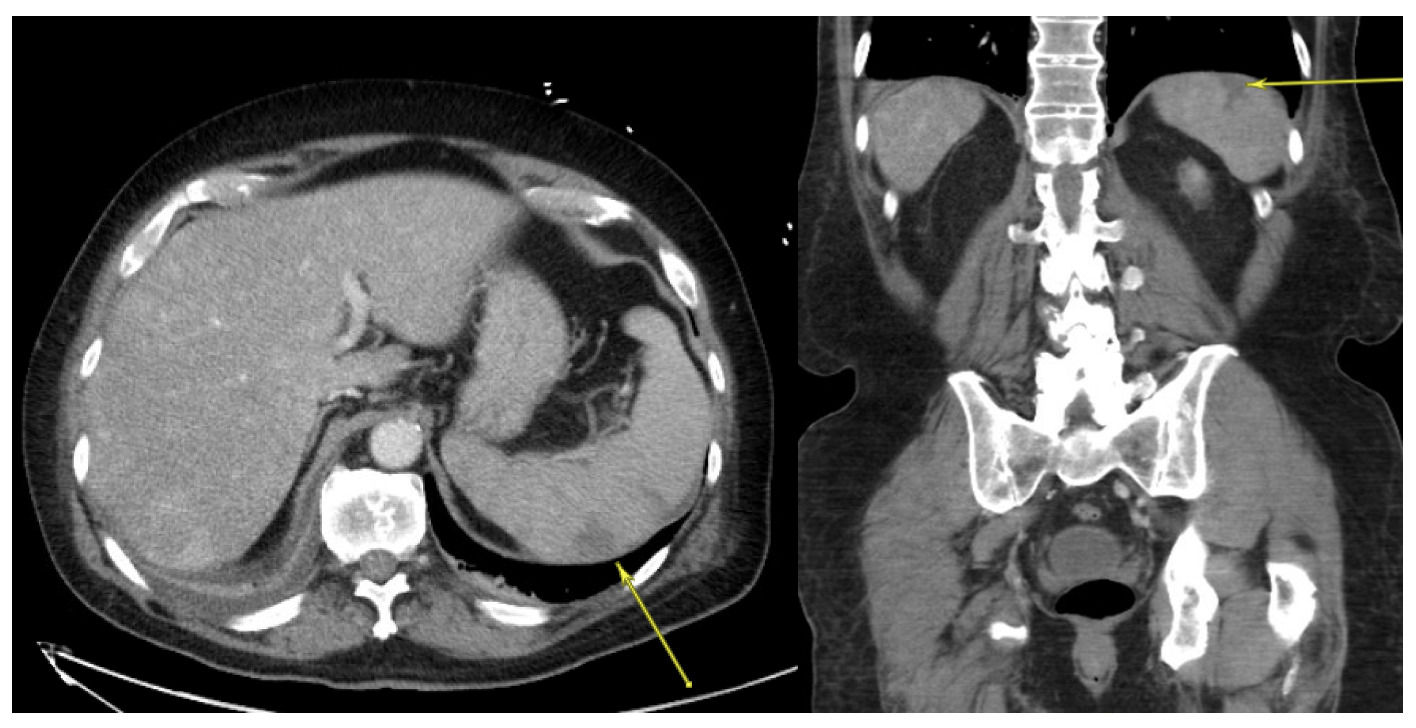

A 75-year-old man with chronic obstructive pulmonary disease (COPD), hypertension, hyperlipidemia, and trigeminal neuralgia presented to urgent care with generalized fatigue, myalgias, subjective fevers, and worsening neuralgia for one week following a golf outing. Peripheral smear revealed a parasitemia level of 8% with a subset of altered, mature red blood cells infected by 1-4 (“tetrad”) small ring parasites consistent with Babesia microti infection. He was started on atovaquone, azithromycin, and empiric doxycycline coverage. His parasitemia level trended from 8% to 16.85% despite receiving this regimen for three days, thus he was switched to quinine and clindamycin and was transferred to a tertiary care hospital for possible exchange transfusion. His platelets continued to fall to 20,000/mm3 and his hemoglobin declined to 10.5 g/dL. A CT of the chest, abdomen, and pelvis with IV contrast revealed a wedge-shaped splenic hypodensity consistent with infarct (Figure 3). Echocardiogram was not suggestive of infective endocarditis or cardiac emboli as the source of infarction. Exchange transfusion was deferred in favor of transitioning his therapy from quinine and clindamycin to atovaquone and azithromycin. He was also treated with doxycycline for presumed anaplasmosis during this time.

His parasitemia level downtrended to 1.15% with this regimen, however he developed acute respiratory failure due to non-cardiogenic pulmonary edema. He was treated with intravenous furosemide. On hospital day five, he was transitioned to oral azithromycin and atovaquone. His platelet count recovered and stabilized at 150,000/mm3. He was started on therapeutic anticoagulation with low molecular weight heparin for his splenic infarct. After an 18 day stay between two hospitals, his parasitemia level was undetectable and he was discharged to a skilled nursing facility on azithromycin and atovaquone. Based on the absence of evidence for other etiologies for splenic infarct, including cardioembolic source and malignancy, this patient’s infarct was treated as a provoked thromboembolic event with three months of therapeutic anticoagulation with apixaban.